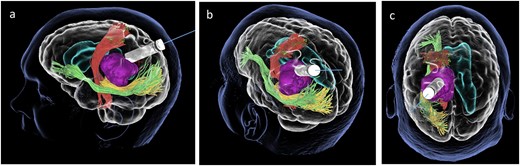

Subsequently, a tsMIPS approach was performed through the intraparietal sulcus. A tubular retractor (NICO BrainPath®) was cannulated 30 mm deep, directly onto the lesion. Following docking of the tubular retractor, an intra-operative CT scan (O-ARM®) was performed, and the resulting images were fused with pre-operative MRI and tractography. The port was identified at the centre of the lesion, with air acting as contrast (Fig. 3). The tumour was centrally debulked, outer sides rolled inwards, and capsule disconnected.

Coronal (a), sagittal (b) and axial (c) views of the merged images from intra-operative CT scans (O-Arm) with pre-operative MRI tractography. The tubular retractor is in situ. (d) Virtual 3D reconstruction of the tubular retractor (brown) in the merged images and its relationship with the tumour (purple), the CST (red), the IFOF (green), and the OR (yellow).